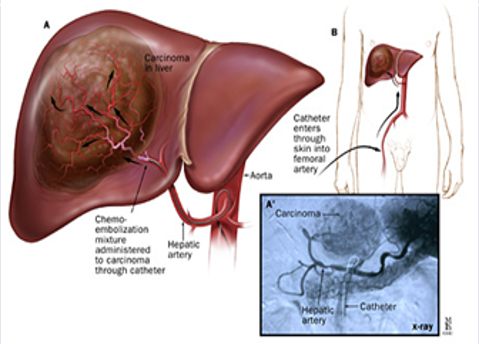

- כימואמבוליזציה טרנס-עורקית (TACE, Trans-Arterial Chemo-Embolization) (תמונה מספר 3) – מערבת הזרקת חומר כימותרפי עם Lipiodol ולאחריהם כיווץ כלי הדם הספציפי עם תרופות אמבוליות. שיטת טיפול זו משיגה תגובה ב-15-55% מהמקרים וכן מאטה את התקדמות הגידול ואת הפלישה המקרווסקולרית (Macrovascular). שיטה זו גורמת לעלייה בהישרדות - כ-20 חודשים בסך הכל. זהו טיפול הבחירה בחולי סרטן כבד ראשוני שאינם נתיחים ואינם מתאימים לטיפולים אחרים (כגון הזרקה מלעורית ואבלציה) ובלבד שאין התפשטות חוץ-כבדית של הגידול או קריש גידולי בווריד השער.

- תופעות לוואי צפויות של שיטה זו הן בחילה והקאות, דיכוי מח עצם (משני להזרקת Doxorubicin שמשפיע סיסטמית) ותסמונת שלאחר אמבוליזציה (חום גבוה, כאבי בטן ודרגה מסוימת של חסימת מעיים). כימואמבוליזציה עם Drug-Eluting Beads (DEB-TACE) מורידה חשיפה סיסטמית ל-Doxorubicin ומערבת חלקיקים זעירים המשחררים תרופות. מחקר שהשווה שיטה זו ל-TACE רגיל מצא יתרון בתופעות הלוואי וביעילות הטיפול[8]